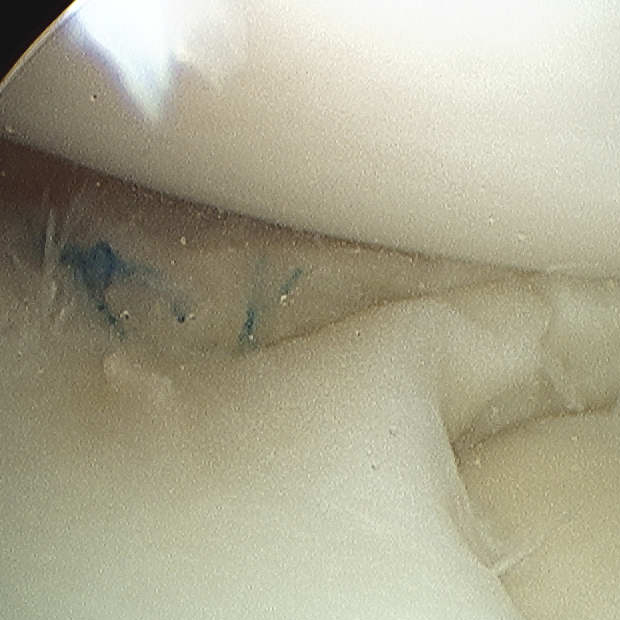

2. Inside out

Technique

Require

- double armed sutures with long flexible needles

- use single or double cannula system

Make open posteromedial / posterolateral approach

- retrieve the sutures needles as they exit the joint capsule

- protects neurological structures (saphenous / CPN) from needle or suture injury

- sutures then tied over capsule

- pass in flexion to protect structures

Pass the needles about the tear

- vertical or horizontal mattress sutures

- absorbable or non absorbable 2.0 suture

- every 2-3 mm

Tie sutures over capsule

- tie in extension or will break when patient extends leg